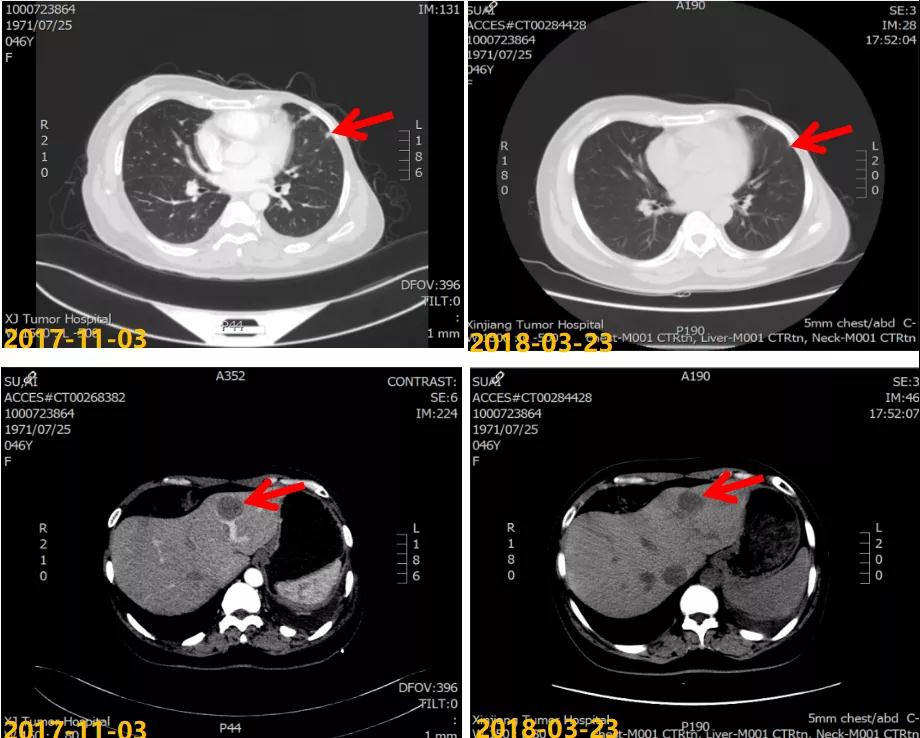

第一次病情进展: 2017-10-22患者因“气喘气憋、呼吸困难20天”就诊我院,胸水超声提示左侧大量胸腔积液,行胸水穿刺引流,查见癌细胞。2017-11-03 CT:两肺多发结节,考虑转移瘤;左侧胸膜斑块状增厚,提示胸膜转移;肝脏多发转移瘤。进一步行肝脏肿块穿刺活检,病理:ER(2+,90%),PR(3+,80%),HER2(2+),Ki-67(+,40%),FISH检测:未观测到基因扩增。

2017-11至2018-03:TX方案6周期(多西他赛120mg d1+卡培他滨1500mg po bid d1-14),化疗期间继续戈舍瑞林3.6mg ih q4w。疗效评估:前四周期略缩小但未达PR,后两周期SD,呼吸道症状明显改善。2018-04行戈舍瑞林3.6mg ih q4w联合氟维司群 500mg im q4w内分泌维持治疗,同时经MDT多学科讨论后行肝脏射频消融术。一线治疗获得36个月PFS。

本例患者为绝经前年轻女性,分子分型为luminal B型(HER2阴性)。术后FEC方案辅助化疗6周期后行戈舍瑞林联合他莫昔芬辅助内分泌治疗。患者于辅助内分泌治疗结束1年内出现双肺、胸膜和肝脏转移,经过肝脏穿刺证实分子分型仍为luminal B型(HER2阴性)。考虑患者继发性内分泌耐药(辅助内分泌治疗时间大于2年复发转移),晚期一线治疗选择TX化疗6周期,肺部、胸膜、肝脏转移灶最佳疗效评价为 SD。维持治疗调整治疗方案为氟维司群+戈舍瑞林,最佳疗效评价为 PR。该患者从一线维持治疗有36个月PFS获益。